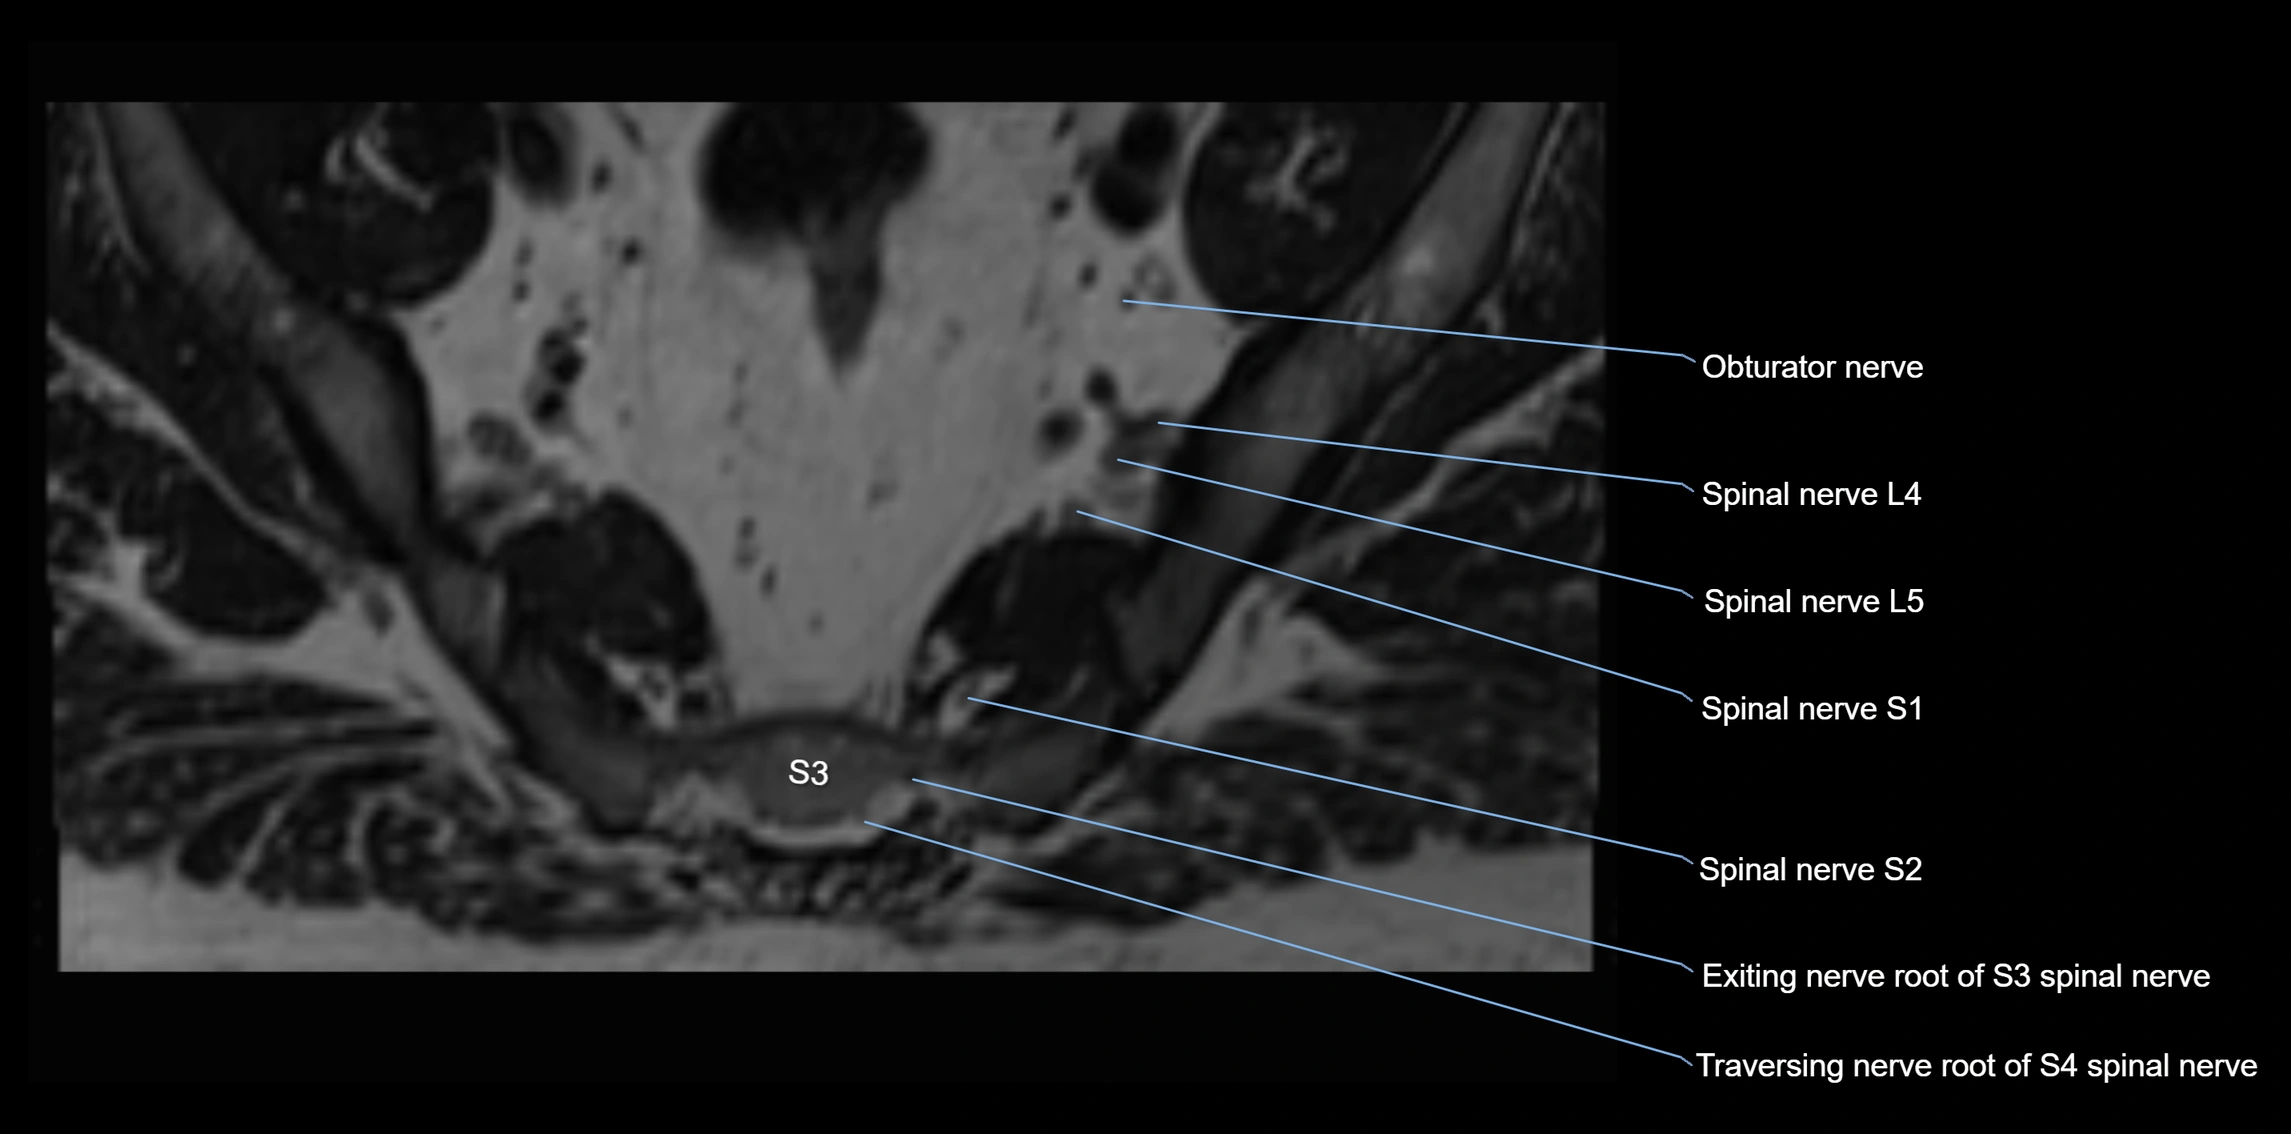

MRI image

image